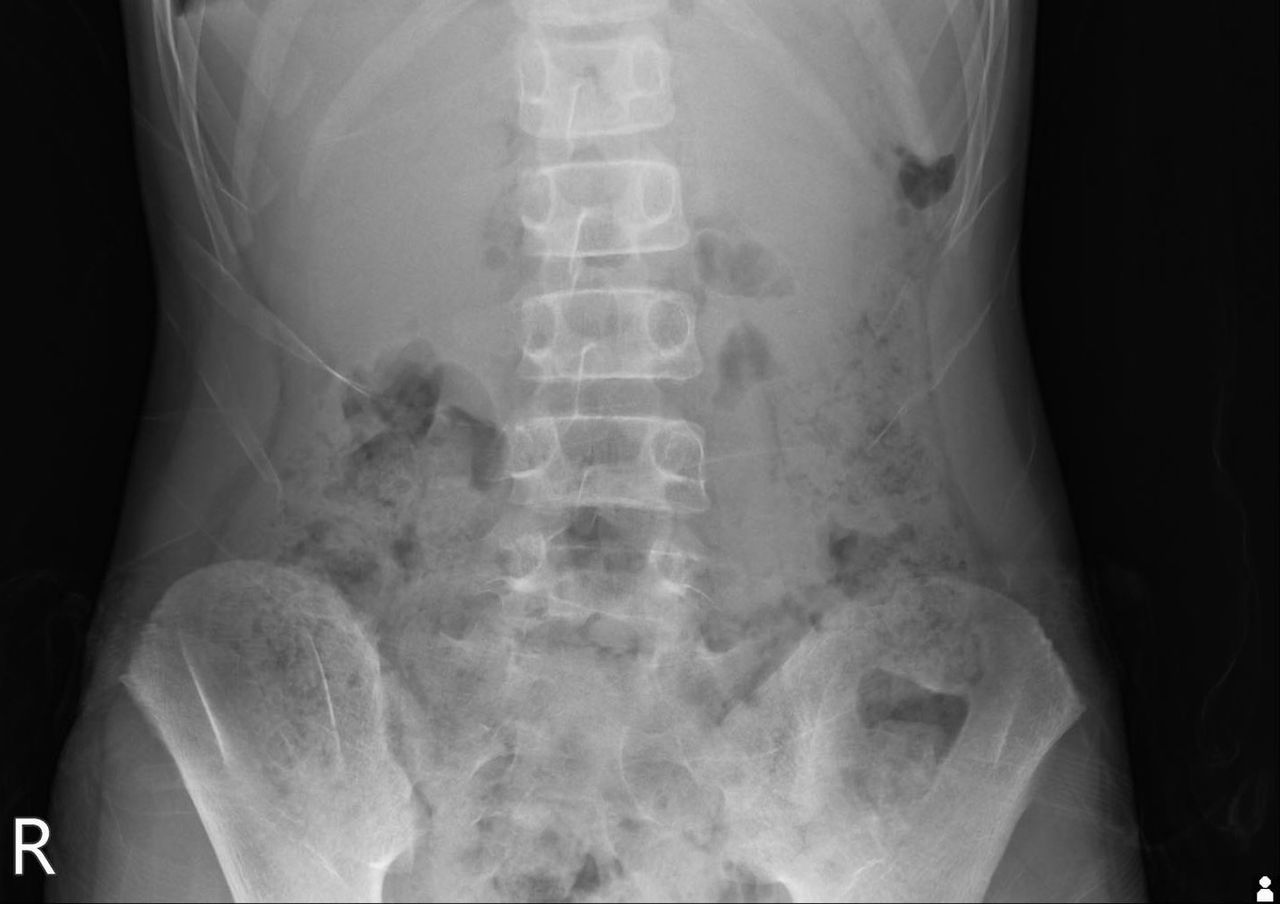

▲謝宗學分享女童的X光片,「可在雙側橫隔膜看到明顯的free air (游離空氣)」。(圖/翻攝「Dr. E 小兒急診室日誌」臉書)

謝宗學交代住院醫師,帶病人去影像科照腹部X光,並提醒他一定要請病人站立照,「腹部X光的結果如我的預期,可以在雙側橫隔膜看到明顯的free air (游離空氣),診斷應該是胃或十二指腸穿孔。」